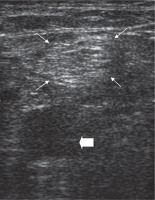

All patients underwent SNB prior to the angiography procedure. Each block was performed by an interventional radiologist (MG) who was experienced in US-guided peripheral nerve block. A posterior popliteal approach to SNB was employed in this study. The patients were placed in the prone position. After skin disinfection, an ultrasound system with a high-frequency linear transducer (9-13 MHz) was positioned to localise the sciatic nerve on the popliteal fossa. After identifying the sciatic nerve as a round, hyperechoic structure (Figure 1), the overlying skin was infiltrated with local prilocaine. A 21-gauge needle was inserted at a 45° to 60° angle to the skin and advanced slowly toward the target nerve in a plane from lateral to medial or medial to lateral direction (Figures 2 and 3). To avoid an incomplete nerve block, the needle insertion point was chosen just above the division of the sciatic nerve. After confirming that the tip of the needle was adjacent to the sciatic nerve, the block was conducted with multiple injections of local anaesthetic to create a circumferential spread around the sciatic nerve (Figure 2 and 3). In all patients, SNB was performed with a standardised mixture of 10 ml of bupivacaine 0.5%, 10 ml of lidocaine 2%, and 10 ml normal saline. The success of the block was defined as a significant relief of pain prior to endovascular treatment. If the patients were not satisfied with pain relief within five minutes, the block was repeated with the same dose of local anaesthetics. Narcotic medications were administered if required. The dose and time of administration were recorded.

Figure 1

Ultrasound image of the pre-injection sciatic nerve in the popliteal fossa. Thin arrows: sciatic nerve; Thick arrow: popliteal artery